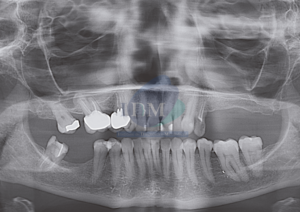

Paciente femenina de 72 años es referido al Instituto de Diagnostico Maxilofacial para una evaluación por imágenes sobre su estado de salud oral general. Al